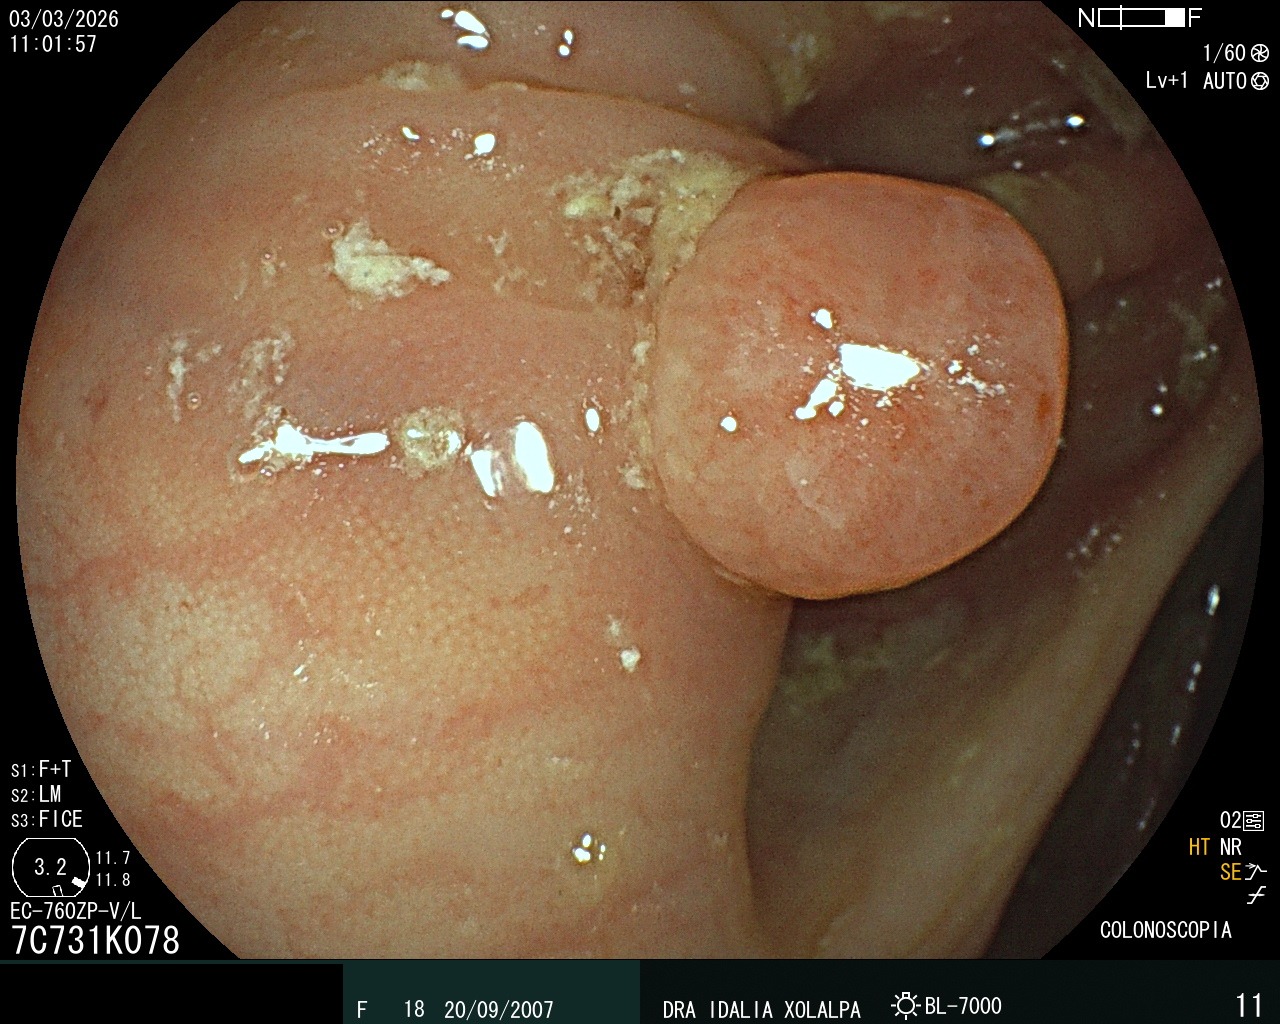

Pólipo en Colon

Detección de pólipo durante colonoscopia